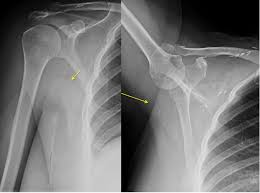

However, pain and additional symptoms. Bones are the most common site of secondary breast cancer, and it tends to affect large bones such as the spine, ribs and shoulder blades, says emma pennery, clinical director of the charity. The earliest sign of breast cancer is often a lump in the breast. Most times, breast pain signals a noncancerous (benign) breast condition and rarely indicates breast cancer. One in six women with breast cancer have symptoms other than a raised lump. But millions of women are surviving the disease thanks in part to early detection and improvements in treatment. A sudden, noticeable new pain is the most common symptom of cancer that has spread to the bone. The development of joint pain is a common symptom of breast cancer metastasizing to the shoulder. Signs and symptoms of local recurrence on the chest wall after a mastectomy may include: This specific patient had shoulder pain as initial manifestation of breast cancer, making the orthopaedist the first doctor she saw. These are some of the most common bone sites to which breast cancer can spread. Grade 3 is an aggressive cancer it does not mean that it cannot be treated. Shoulder pain in breast cancer survivors is a common condition that should not be ignored.